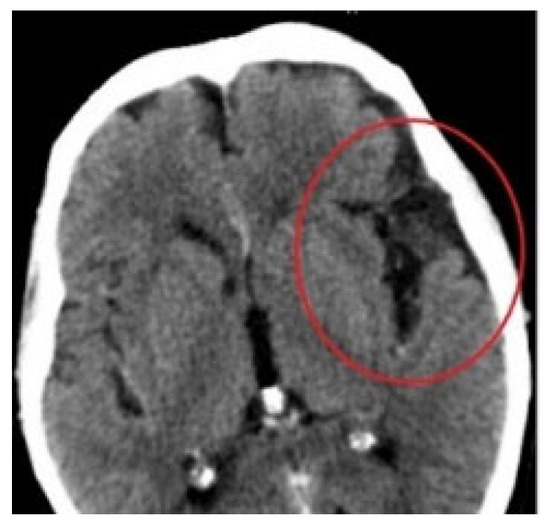

Another medical case meeting was held, this time with specialists in neurosurgery and maxillofacial surgery. Frontal sinus obliteration was planned: however, a defect was noted in the posterior wall of the frontal sinus (Figure 7) together with a 10 mm-wide fluid space in the temporoparietal region (Figure 8) with a density of 15 Hounsfield units, a dilated Sylvian fissure. Therefore frontal sinus cranialization was eventually proposed.

Figure 7. Defect in the posterior wall of the frontal sinus, CT scan.

Figure 8. Fluid space in the frontotemporal region, CT scan.